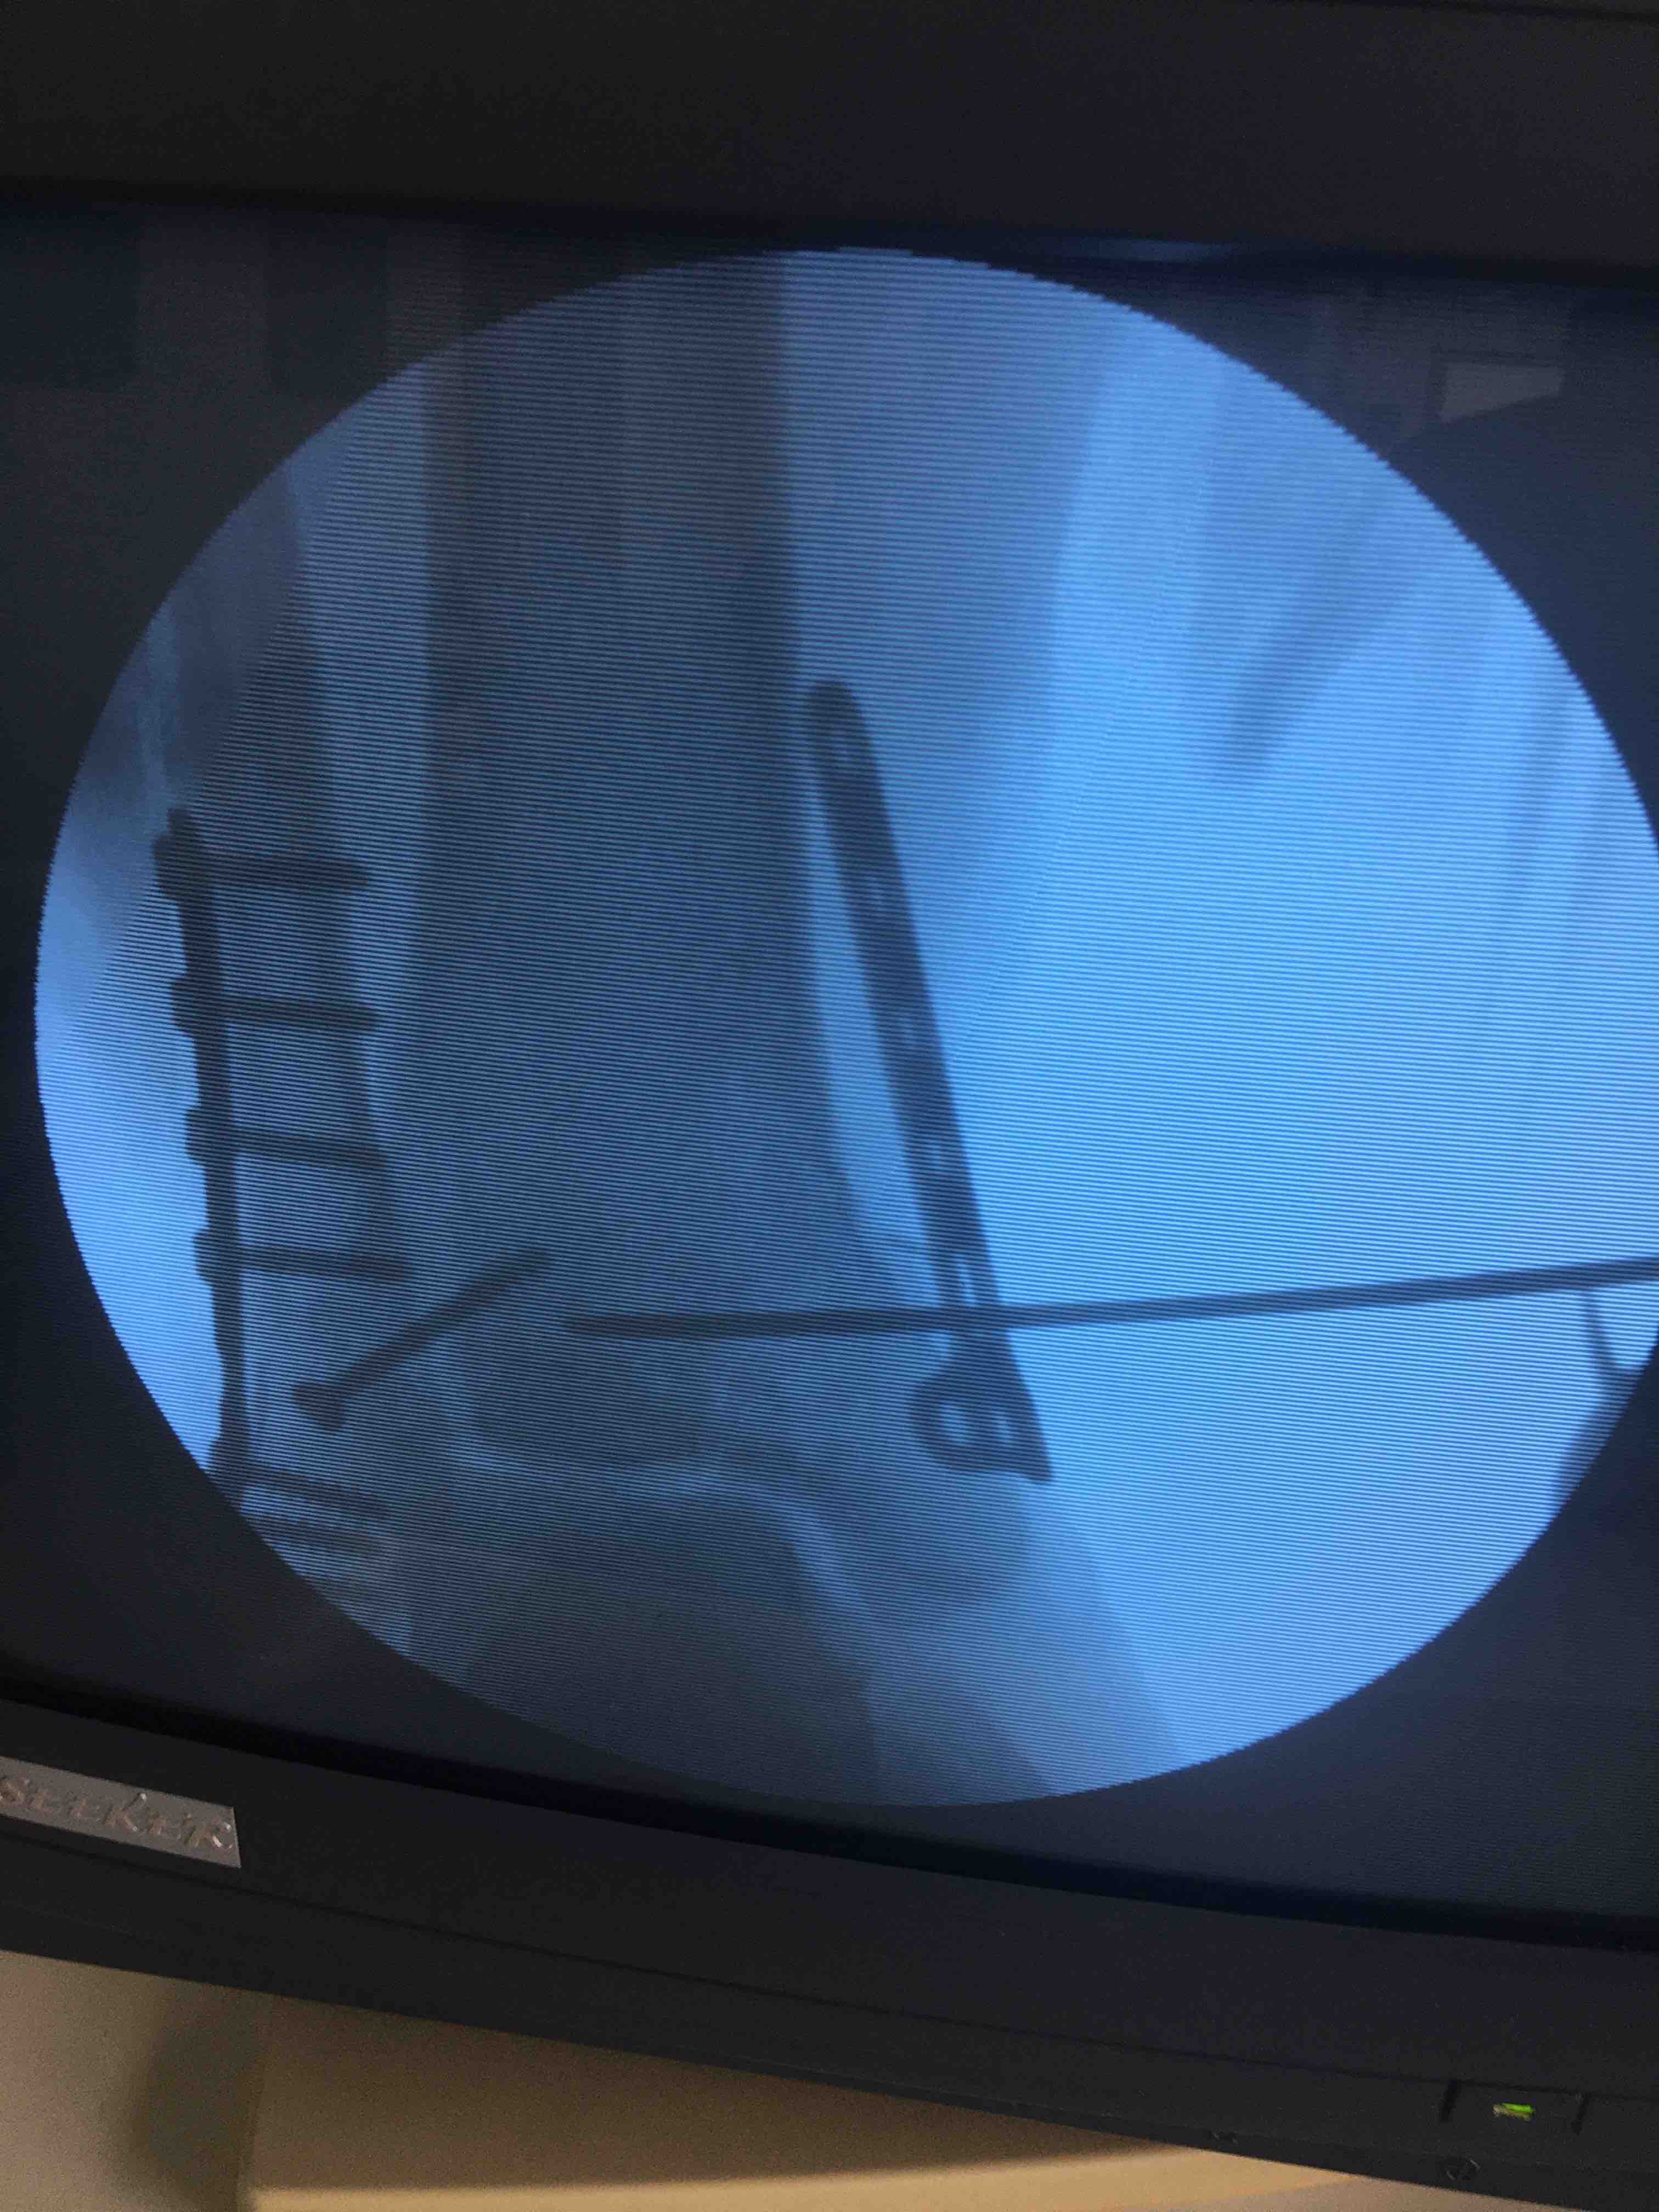

三踝骨折orPilon骨折?(切复内固定术)

坠落伤后右踝肿痛,畸形,活动受限1小时入院。既往身体健康,无特殊不良嗜好。

右踝部肿胀,畸形,皮色青紫,皮温高,压痛及叩痛明显,可及骨擦感,关节活动受限,末梢血运感觉正常。

在腰麻下行切复内固定术,内踝处选用锁定钛板,撬拨复位关节面。